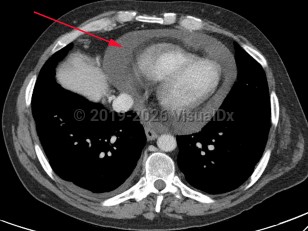

Pericardial effusion

A pericardial effusion (PE) is an accumulation of an abnormal amount of fluid within the pericardial cavity, usually from inflammation. It may be caused by local or systemic disorders or may be idiopathic. It is typically secondary to injury to the pericardium, such as pericarditis. In more than half of cases, PE is associated with a known or suspected underlying process.

Treatment is dependent on the severity of the disease, the underlying cause, and whether there is or may be a decrease in heart function.